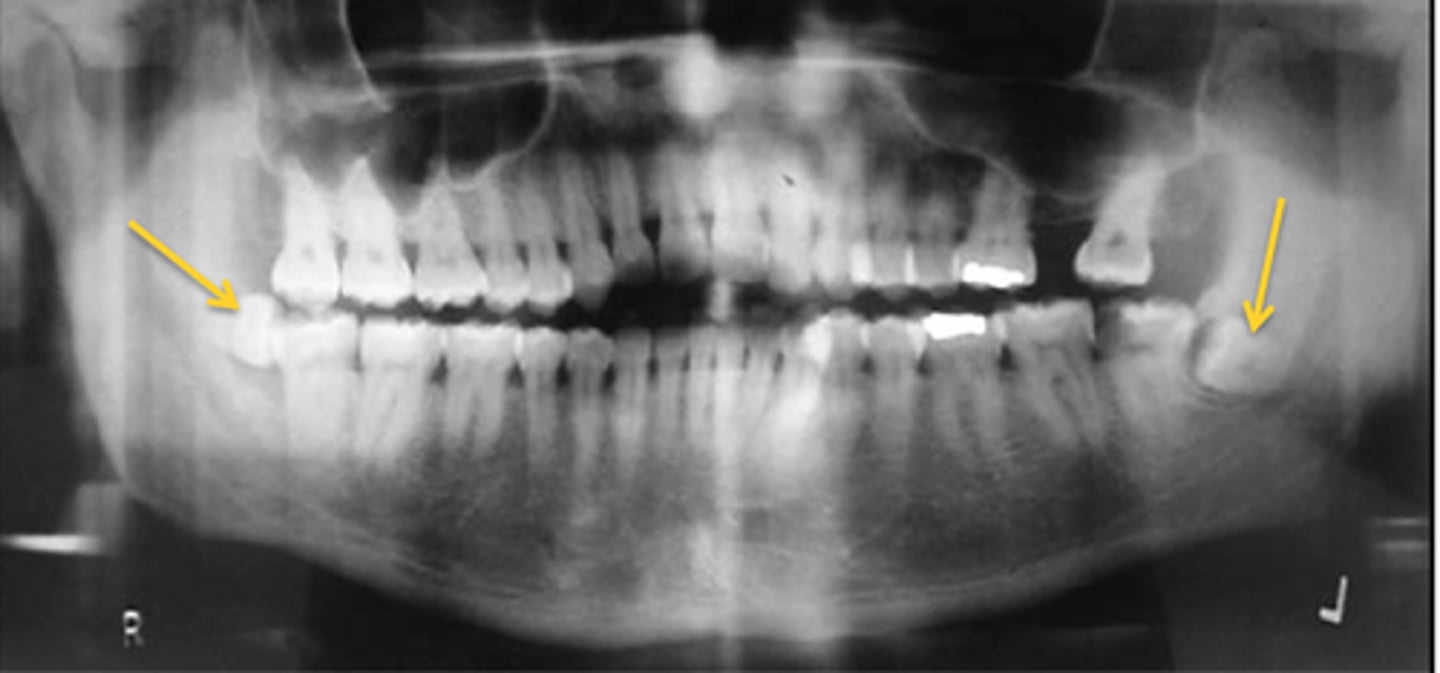

What is the demographic affected by Cemento-osseous Dysplasia?

AA/Asian women

What teeth does Cemento-osseous Dysplasia affect?

Mandible and maxilla, anterior teeth

What distinguishes the Florid type of Cemento-osseous Dysplasia?

>2 quadrants affected